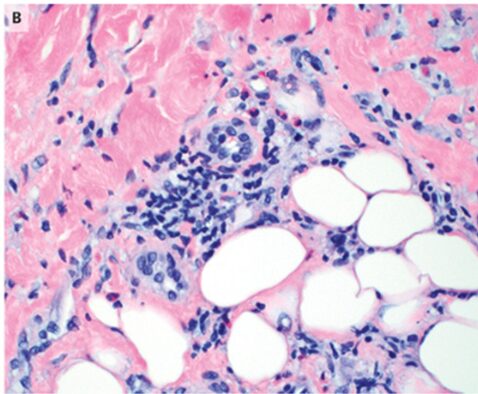

確定診断のため、皮膚生検施行。

病理所見としては、真皮と皮下組織の間質ならびに血管周囲に好酸球とリンパ球の浸潤を認めた。